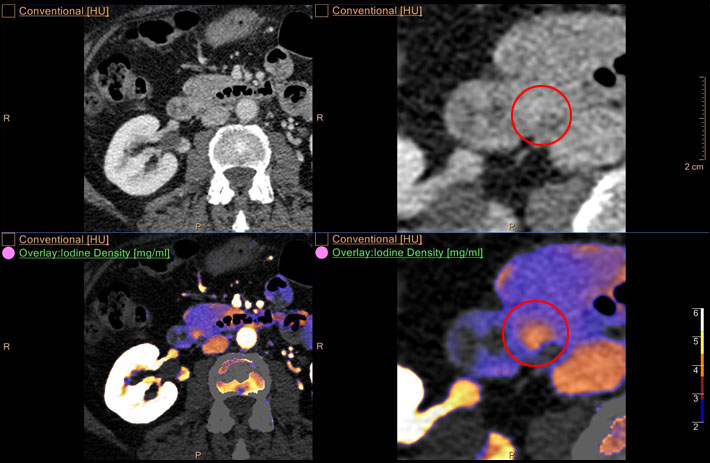

Mit dem Spektral-Detektor-CT werden Spektraldaten automatisch bei jedem Scan erfasst. Die Informationen stehen jederzeit auf der Scankonsole, der CT-Workstation sowie an jedem PACS-Arbeitsplatz zur Verfügung, sodass es nicht notwendig ist, den Patienten erneut zu scannen, bspw. wenn initial zufällige Anomalien festgestellt wurden. Dadurch profitieren Anwender durch eine höhere Diagnosesicherheit und weniger Nachuntersuchungen auf anderen bildgebenden Systemen. Unsere Fallsammlung zeigt, welchen klinischen Mehrwert der Spektral-Detektor-CT in unterschiedlichsten Anwendungsbereichen in der klinischen Routine bringt. Jede Woche gehen neue Fälle live.